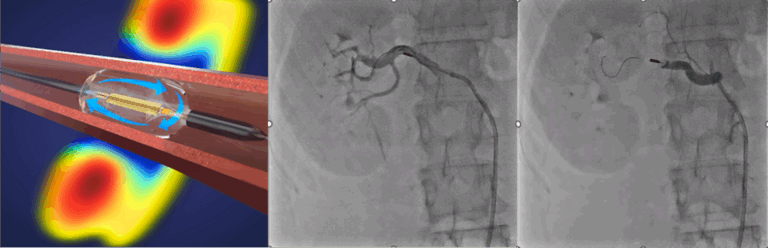

2. 超音波カテーテル: 超音波を発するバルーンカテーテルを用いて、腎動脈周囲の交感神経を全周性に焼灼します。(図2および動画2参照)。

図2 超音波によるRDN